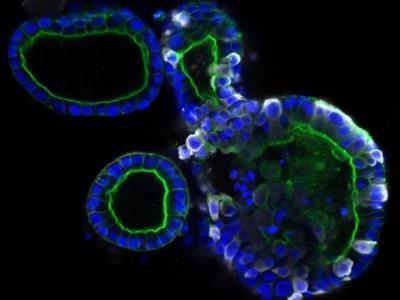

स्कॉटलँड स्कूल ऑफ लाईफ सायन्सनी कोरोना व्हायरसच्या काही प्रिंट्स फोटो दाखवले आहेत. त्यात असं दिसून येत आहे कोरोना व्हायरसचं आतड्यांवर फक्त संक्रमण होत नसून कोरोना आतड्यांमध्ये वेगाने पसरत जातो.

माणसाच्या शरीराला संक्रमित करून आतड्यांपर्यंत पोहोचत असलेला कोरोना व्हायरस पांढऱ्या रंगाचा दिसतो. कोरोनाचे निरक्षण करण्यासाठी शास्त्रज्ञांनी अल्ट्रा पॉवरफुल मायक्रोस्कोपचा वापर केला.

शरीरातील कोरोना व्हायरसची माहिती देणारे हे फोटो ३० ते ५० गीगाबाईट्सचे आहेत. स्कूल ऑफ लाईफ सायन्सचे क्वारंटाईन सेल बायोलॉजी प्रोफेसर यांनी सांगितले की, कोरोना व्हायरस आतड्यांपर्यंत पोहोचून शरीराचं नुकसान करत असतो. आतड्यांमध्ये व्हायरसची संख्या वेगाने वाढत जाते.

संशोधकांनी यावेळी माणसांच्या आतड्यांचे परिक्षण करत असताना एका तपासणी ट्यूबमध्ये यशस्वीरित्या व्हायरसच्या नमुन्यांना विकसीत केलं आहे. यानंतर व्हायरसचा परिणाम आतड्यांवर कशा पध्दतीने होत आहे. यावर परिक्षण करण्यात येईल.